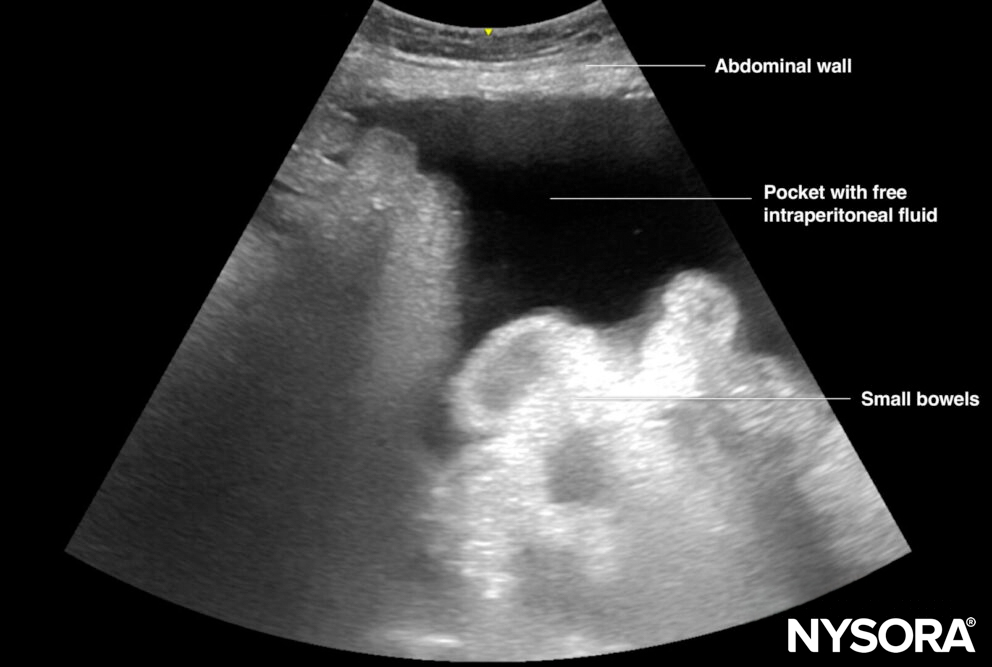

- Scan with a curvilinear transducer the LUQ, RUQ, and pelvic areas, to assess the presence and the amount of free fluid. Then scan both lateral lower quadrants and identify an ‘ideal’ insertion area. The space where there is enough free fluid between the abdominal wall and the viscera is called ‘a pocket’.

Illustration of a pocket with free intraperitoneal fluid.